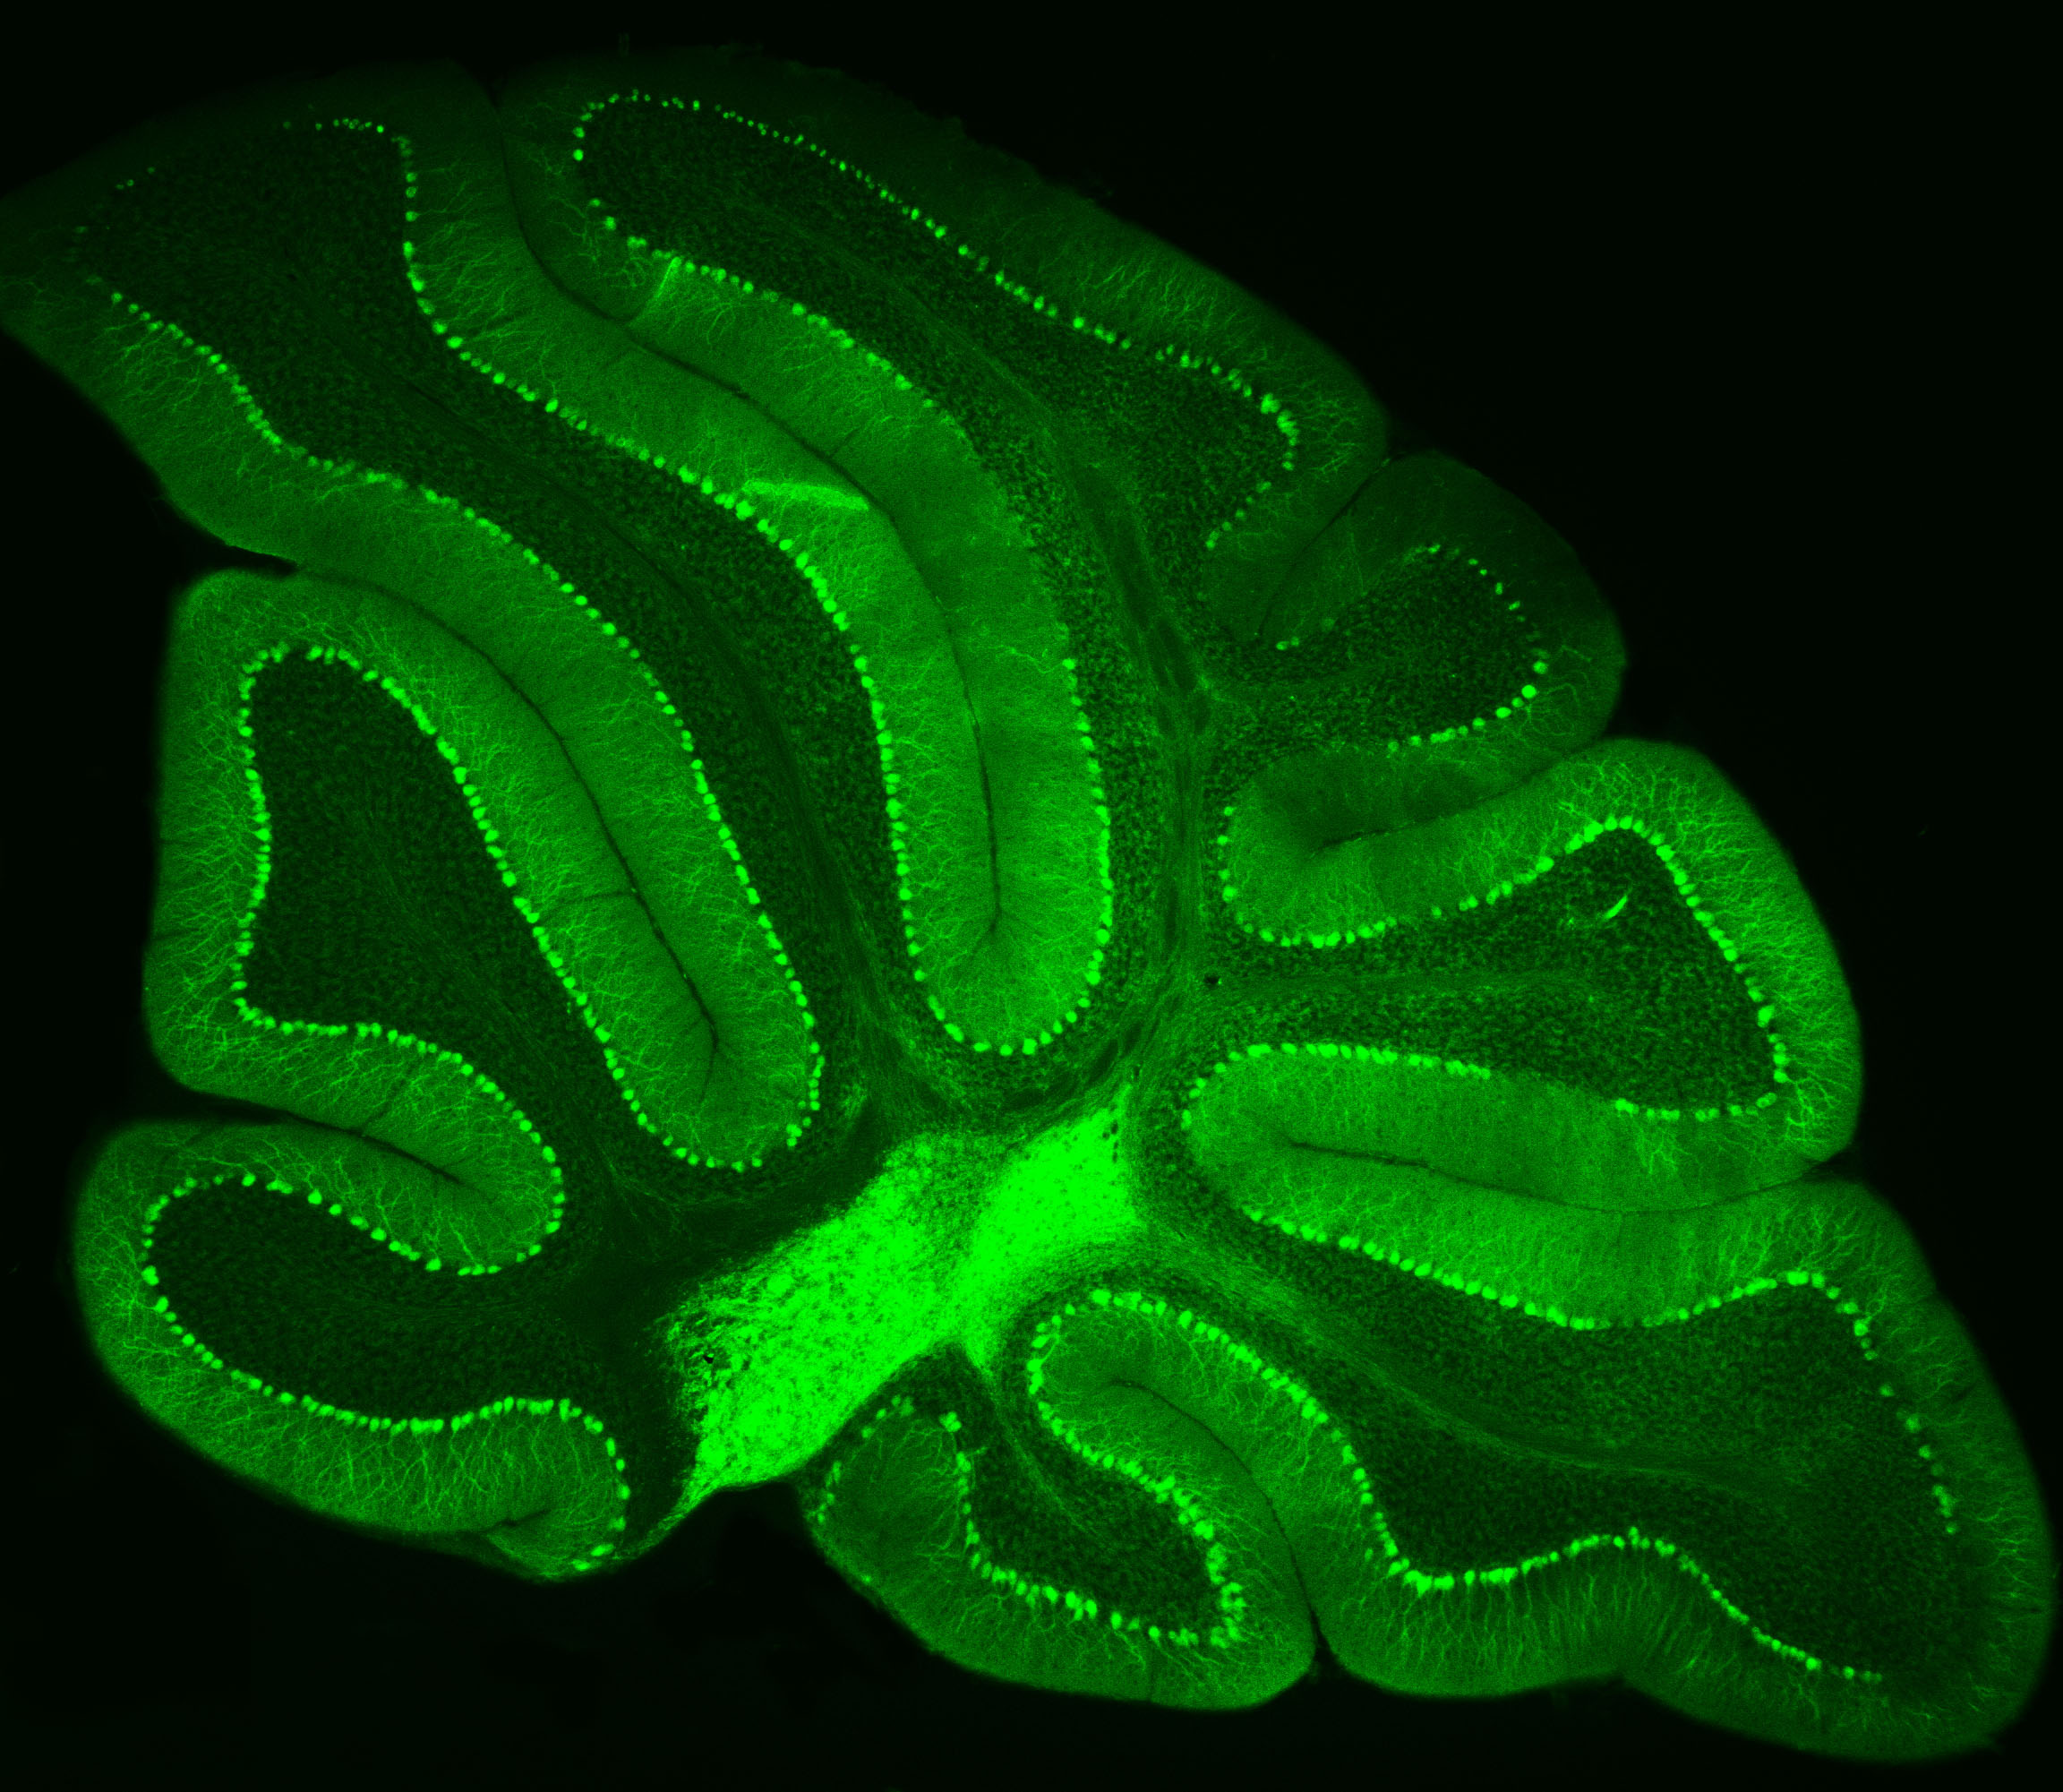

Purkinje neurons from an animal model are labeled with green fluorescent protein (GFP), which causes them to glow bright green. Credit: Pennington Biomedical

Purkinje neurons from an animal model are labeled with green fluorescent protein (GFP), which causes them to glow bright green.

At Pennington Biomedical Research Center, scientists often study the brain by highlighting specific cells so they can be seen more clearly under a microscope. This technique was recently used by Dr. Yanlin He, associate professor and director of the Brain Glycemic and Metabolism Control Laboratory, who is examining Purkinje neurons in the cerebellum.

Purkinje neurons are best known for helping control movement and motor learning, but researchers are discovering they may have other important roles in the body as well, such as controlling energy balance and blood sugar.

By making these neurons glow green, Dr. He and his team can see their complex branching shapes and how they connect within the cerebellum’s neural network.

This technique also allows researchers to perform electrophysiology recordings, which measure the electrical activity of the cells in a laboratory setting. Their work could help scientists better understand how the brain helps regulate metabolism and overall health.